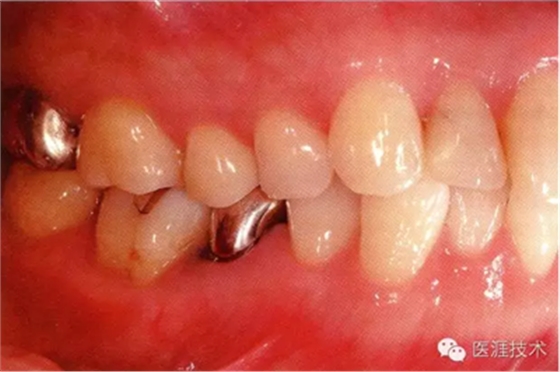

65歲男性的健康口腔內(nèi)部

65歲男性。糖尿病與高血壓病史,目前治療中,40歲左右戒煙。有唾液減少傾向,但目前尚未見對牙齒及牙周組織的影響。初診時齲齒治療后,來院就診保養(yǎng)10年,雖因刷牙過度有牙齦萎縮,但牙齒及牙周組織仍保健康。如可妥善維持菌斑控制,則可維持牙周組織健康,不會減少牙周組織。